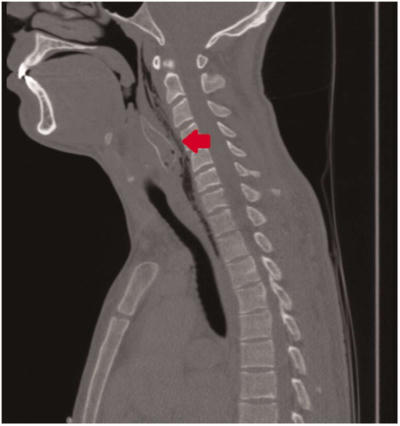

Theo các bác sĩ, bệnh nhân uống một ngụm bia lớn rồi nuốt con cá dài khoảng 5 cm. Tuy nhiên, con cá quẫy mạnh, kéo căng vây và các gai nhọn trên mình để không bị trôi xuống họng chàng trai. Cơ thể nó cũng tiết ra chất độc.

Con cá mắc kẹt trong họng, chàng trai vô cùng hoảng loạn. Anh cho hai ngón tay vào móc họng nhưng không được. Một người bạn tiến hành thủ thuật Heimlich để bỏ dị vật song cũng vô hiệu. Bệnh nhân nôn mửa và ho ra máu.

Vài giờ sau dù nhóm bạn tìm mọi cách xử lý bằng bia, mật ong và kem, con cá vẫn nằm trong cổ họng chàng trai. Cuối cùng, anh phải đến cơ sở y tế.

Các bác sĩ Trung tâm Y tế Đại học Erasmus phải phẫu thuật để lấy con cá, lúc đó đã chết, khỏi họng bệnh nhân. May mắn, thực quản anh này không bị thủng, cũng chưa nhiễm chất độc từ con cá.